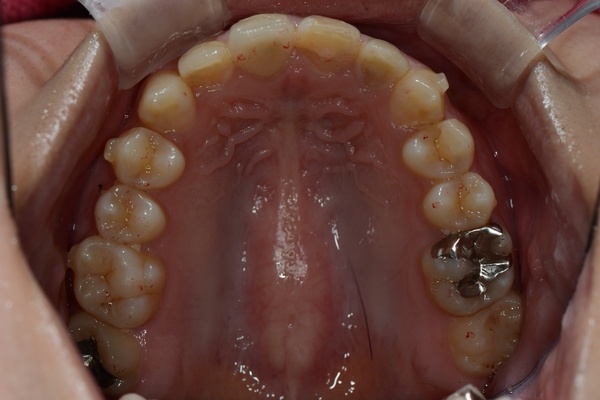

ガタガタとした歯並びや八重歯(叢生)CASE65